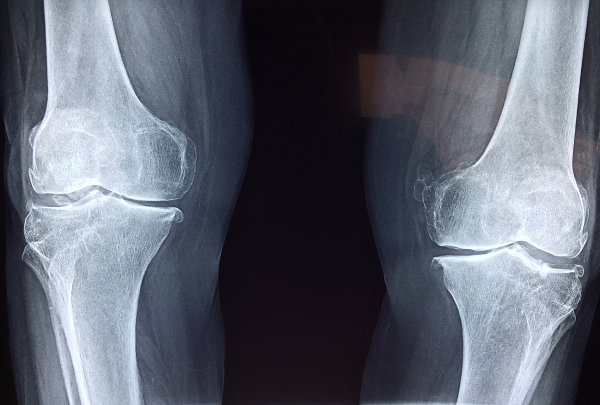

40대에 접어들면서 관절의 퇴행성 변화가 시작되면서 무릎이나 고관절 통증을 경험하는 경우가 많습니다. 콘드로이친은 이러한 관절 통증을 줄이는 데 도움을 줄 수 있습니다. 특히 관절염으로 인한 통증을 줄여주는 데 효과적이라는 연구 결과가 있습니다. 콘드로이친은 염증을 감소시키고 연골 조직을 보호하여 관절의 움직임을 개선하는 데 도움을 줍니다. - 연골 보호 및 재생 촉진

콘드로이친은 연골을 보호하고 연골 세포의 재생을 촉진하는 역할을 합니다. 40대 이후에는 연골의 손상이 점차 가속화되기 때문에, 콘드로이친이 연골의 주요 구조물인 프로테오글리칸과 콜라겐의 생성을 도와 연골 손상을 줄이는 데 기여합니다. 이로 인해 관절의 유연성을 유지하고 손상된 연골을 회복시키는 데 긍정적인 영향을 미칩니다. - 수분 유지 및 충격 흡수

연골은 관절의 움직임 동안 충격을 흡수하는 역할을 합니다. 콘드로이친은 연골 내의 수분을 유지해 이러한 충격 흡수 능력을 향상시킵니다. 이는 특히 40대 이후 무릎과 같은 관절에 가해지는 부담을 줄여주어 장기적으로 관절 건강을 유지하는 데 중요한 역할을 합니다.